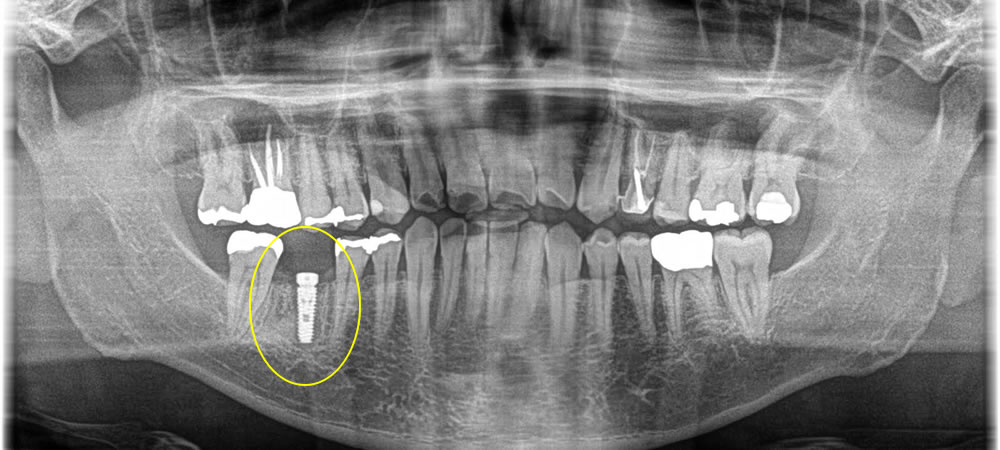

インプラント治療完了後のレントゲン・口腔内写真

その後、インプラントと骨がしっかり結合したのを確認し、上部にジルコニアの歯を作成しました。結果しっかりと物を噛む事ができ、自然な歯になりました。

※ジルコニアのかぶせ物は何かあった時に外す事ができるよう、スクリューリテインにしています。